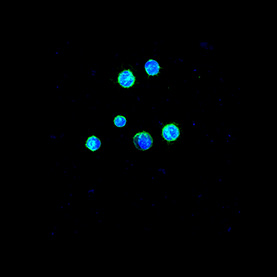

Many processes within the body are changed by the presence of cancer. These images show the response of microglia, immune defense cells in the brain, to cancer cells. When microglia encounter glioblastoma multiforme, one of the most aggressive brain cancers, they shift from a relaxed, elongated shape to a rounded, ready-for-combat conformation.

These images echo the work of Anna Atkins, a British botanist and photographer who used a contact printing technique called cyanotyping to capture the form of plants and algae. Emily Chen’s work similarly seeks to explore biological function, in this case the immune response to brain cancer, by capturing and comparing biological forms.

First Impressions

Jee-Wei and Emily Chen

Brendan Harley Laboratory

Zeiss LSM 710 Confocal Microscope

National Institutes of Health